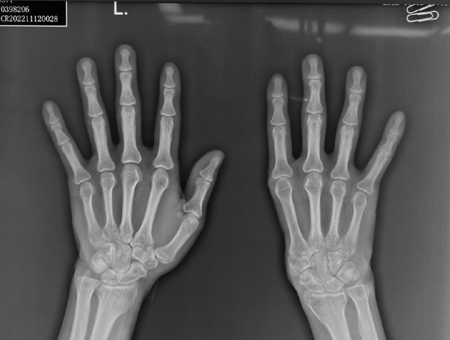

伤口顺利愈合了,但生活的打击才刚刚开始。由于创伤范围大,伤后拇指及第一掌骨、大鱼际软组织均完全缺损,整个手掌仅剩下四个掌骨及四个手指,右手的功能受到严重影响,劳动能力严重下降。对于正值壮年的张先生来说,作为家庭的顶梁柱,上有老下有小,挣钱养家是理所当然的责任,但右手功能的缺损却让他无能为力。

陈山林团队接诊后,经过检查,发现张先生拇指完全缺损,大鱼际部分完全缺损,自大多角骨以远骨关节完全缺损,在分型上属于六度缺损,几乎是最重度的分型了。张先生坚决拒绝从髂骨取骨等其它传统方案,要求利用3D打印技术为他打印掌骨和关节。结合患者要求,经治疗组讨论,陈山林团队决定利用3D打印技术自体结合组织游离移植技术再造第一掌骨系列。

3D打印技术再造拇指并不是直接打印出一个拇指移植到手上,目前医学还无法达到这一步。这个技术的本质,是将双侧手的影像资料数字化,利用电脑软件将伤侧手缺损的部分在健侧手上标记出来,再通过镜影技术将再造所需的部分生成患侧的形状,用3D打印机打印出金属假体,再与自身组织移植结合,从而再造出所需要的人体部位。对于这个患者,需要打印的成分是第一腕掌关节及第一掌骨。